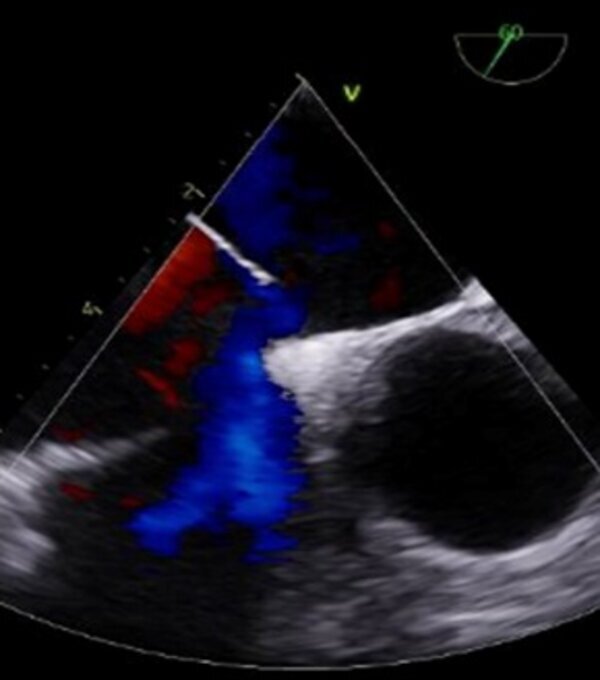

Atrial septal defect (ASD) is a common cardiac defect with significant implications if left untreated. Although open heart surgery is the traditional approach, transcatheter closure devices, such as the Amplatzer™ Septal Occluder Device, have gained prominence due to advantages like shorter hospital stays and reduced costs. Among potential complications, device migration is a rare complication, with an incidence of 0.5 to 1.1%. We report a rare case of migration of an Amplatzer™ device in an asymptomatic patient, diagnosed 6 months after its implantation. After detecting the issue, the medical team opted for percutaneous device removal followed by open surgery to correct the ASD. In conclusion, managing Amplatzer™ device embolization requires careful consideration of the patient's circumstances and device anatomy. This case highlights the importance of correlating clinical and imaging findings when selecting the management approach and assessing the feasibility of a less invasive approach in cases of late migration.